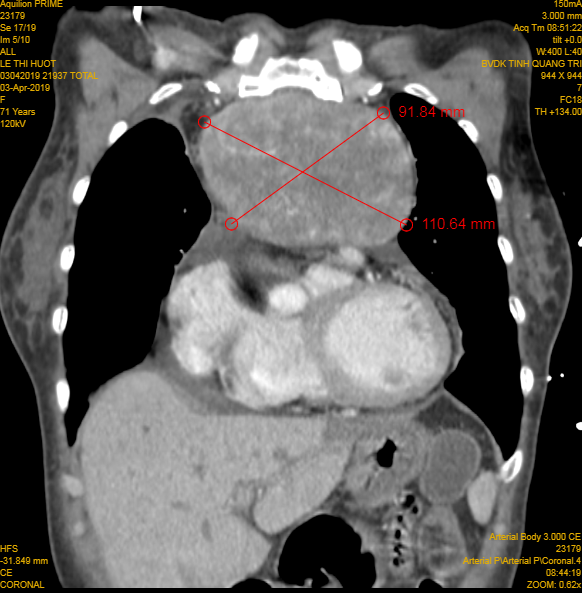

Hình ảnh khối u lớn được chụp lại. Ảnh: BV cung cấp.

Bác sĩ Nguyễn Xuân Dũng - Trưởng khoa Ung bướu Bệnh viện Đa khoa tỉnh Quảng Trị cho biết, kíp mổ thuộc Khoa Ung bướu đã tiến hành mở ngực đường giữa, cắt xương ức, tiếp cận khối u, cô lập các mạch máu nuôi u, bóc tách khối u có kích thước 12 x10 cm, nặng khoảng 1 kg ra khỏi thành ngực thành công sau 3h.